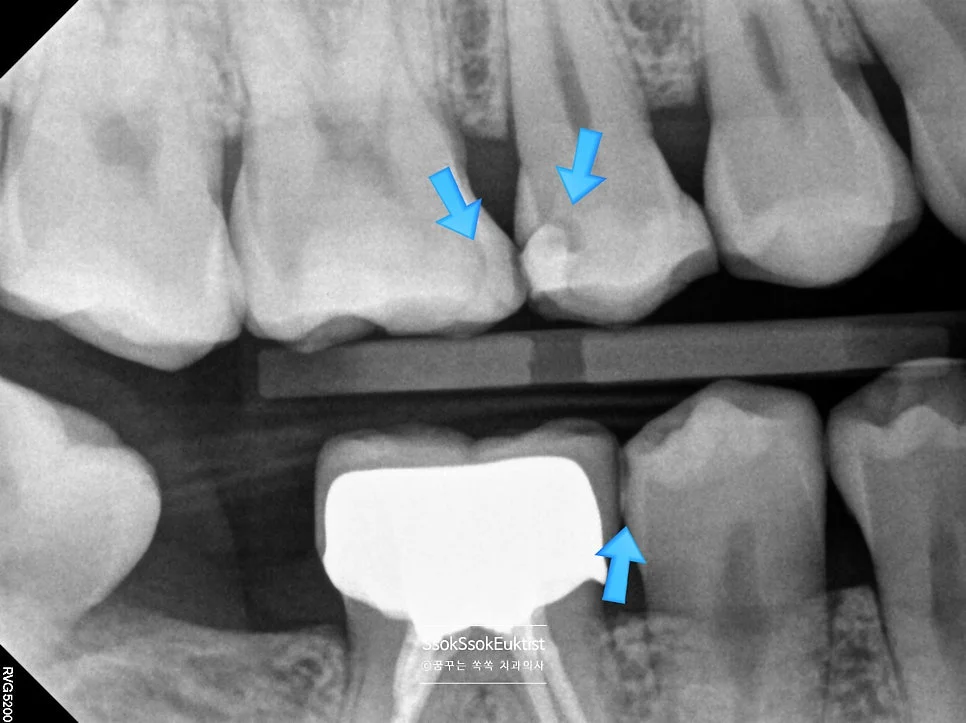

치아 사이를 가장 잘 볼 수 있는 교익 방사선(Bitewing X-ray) 사진을 통해 정확한 충치 진단을 시도합니다.

교익 방사선 사진을 촬영하였을 때, 치아의 가장 바깥 흰색 재질(법랑질)과 안쪽 회색 재질(상아질)을 나누는 선이 검은 음영으로 끊긴 느낌이면 충치로 진단합니다!

(위 사진에서 파란색 화살표로 표시된 부분)

구강 사진에서 하얀색 화살표는 충치의 위치를, 파란색 화살표로는 해당 치아를 번호로 기재하였는데요. 각 치아의 치료 계획에 대해 말씀드리겠습니다.

- 2번 치아 → 충치가 있는 면과 기존 수복물을 모두 포함하는 치료 → 크라운 치료

- 1번 치아 → 2번 치아의 크라운 치료 시 인접한 면을 육안으로 확인 후, 치료가 필요한 만큼 충치가 있다면 레진으로 간단히 치료 (충치가 없으면 치료 X)

- 3번 치아 → 충치가 있는 면과 기존 수복물을 모두 포함하는 치료 → 크라운 치료

- 4번 치아 → 3번 치아의 크라운 치료 시 인접한 면을 육안으로 확인 후, 충치가 있다면 레진으로 간단히 치료

- 5번 치아 → 충치가 있는 면이 인접한 치아에 의해 막혀 있으므로 → 인레이 치료

- 6번 치아 → 충치가 있는 면이 인접한 치아에 의해 막혀 있으므로 → 인레이 치료

조금 어려울 수 있습니다만 천천히 설명드리겠습니다!

총 크라운 2개, 인레이 2개, 레진 가능성 치아 2개, 사랑니 발치 1개입니다.